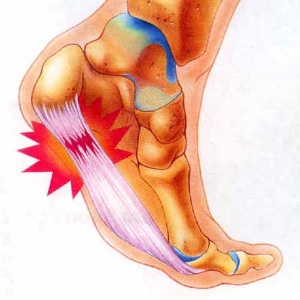

Причиной таких жалоб становится появление костного выроста (остеофита) в месте соединения пяточной кости и ахиллова сухожилия на фоне хронического воспаления. У многих возникает вопрос о том, что делать с такой проблемой и как убрать шип на пятке. В статье пойдет речь о лечении пяточной шпоры в домашних условиях и народными средствами.

Появлению пяточной шпоры предшествует длительная воспалительная реакция, которая изначально развивается в мягких тканях сухожилия, а затем переходит на связочный аппарат и кости.

Костные структуры реагируют на повреждение усилением регенеративных процессов, что приводит к появлению на них наростов. В результате образуется костный вырост, который и становится главной причиной болевых ощущений.